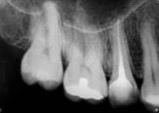

antes depois